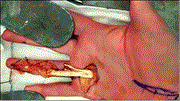

Closed traumatic avulsion of both ring finger flexors with successful primary repair more than 4 weeks after injury and a review of the literature

Miguel A Johnson and James Colville

Journal of Surgical Case Reports, Volume 2020, Issue 7, July 2020, rjaa160, https://doi.org/10.1093/jscr/rjaa160